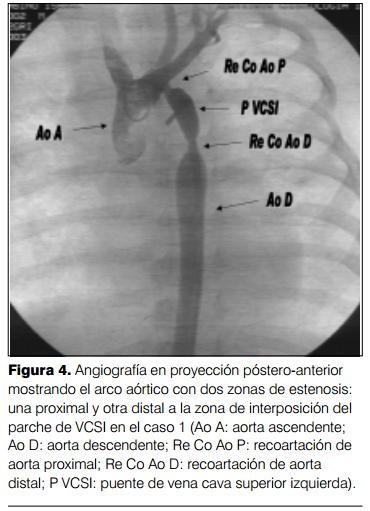

A la edad de 4 meses comienza con polipnea que va en aumento progresivo, comprobándose en el examen clínico los signos de recoartación de aorta. El ecocardiograma confirmó la presencia de recoartación significativa. Se traslada al ICI y se procede a efectuar cateterismo cardíaco que muestra un gradiente de 40 mmHg entre aorta ascendente y aorta descendente, con dos zonas de estenosis, una proximal y otra distal en el puente de vena cava superior izquierda, procediendo a efectuar angioplastia con catéter balón GHOST de 5 x 2 mm, quedando un gradiente residual de 10 mmHg con buena evolución posterior, persistiendo moderada hipertensión arterial pulmonar (en control con ecocardiograma doppler) en un paciente asintomático (figuras 4, 5,y 6).